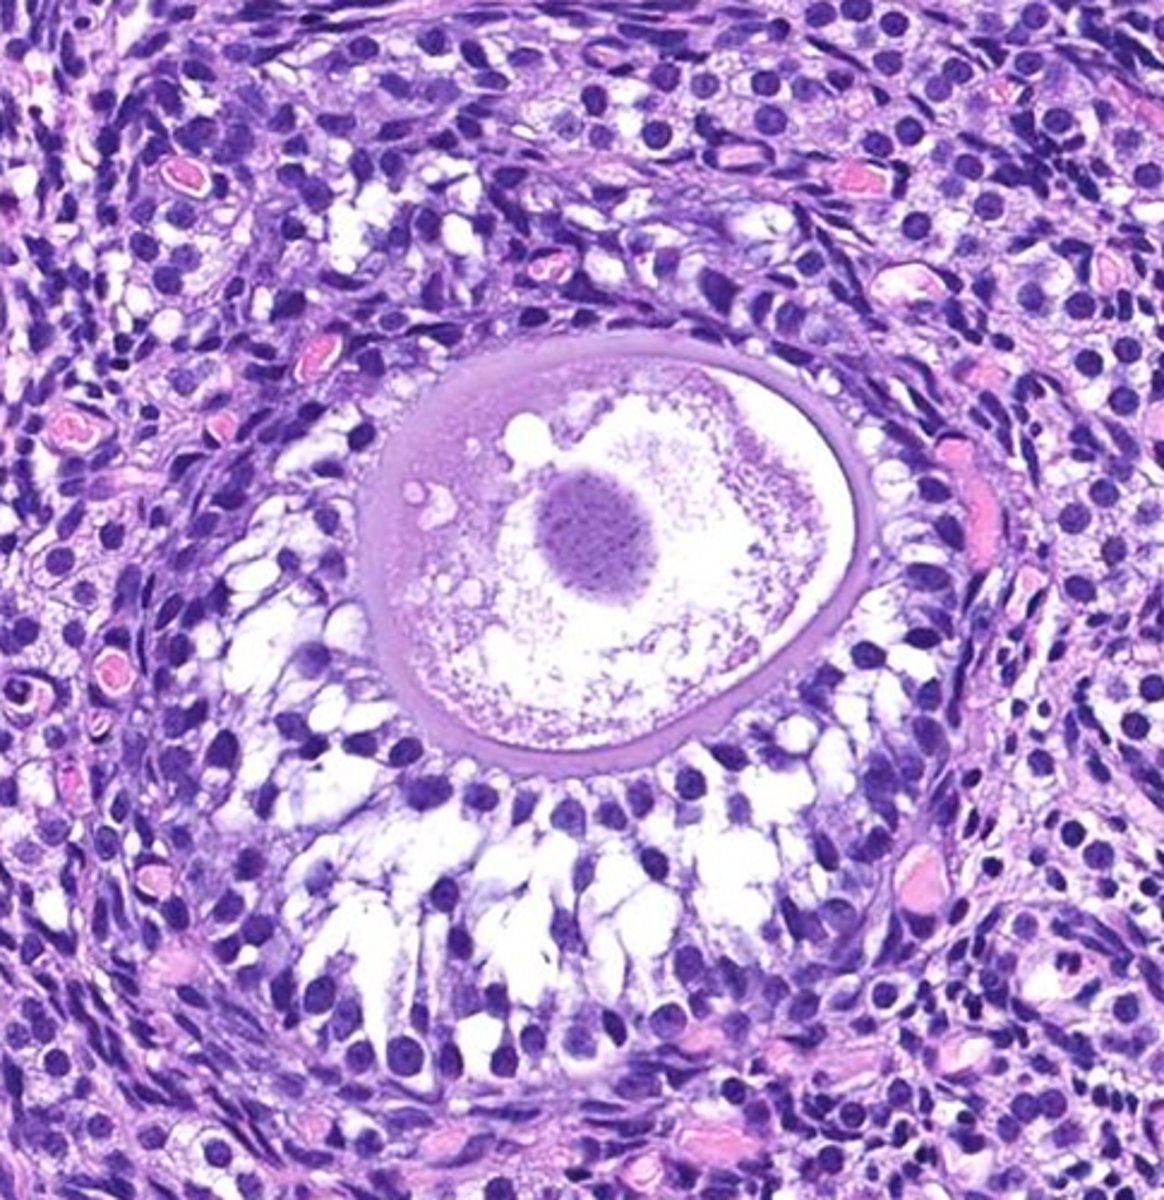

this is a _____ follicle

antrum

the fluid filled space, marked by the X, is called the _____

cumulus

the yellow cells surrounding the oocyte in the antral follicle are called ____ cells

Graafian

antral follicles, or tertiary follicles, are also called ______ follicles